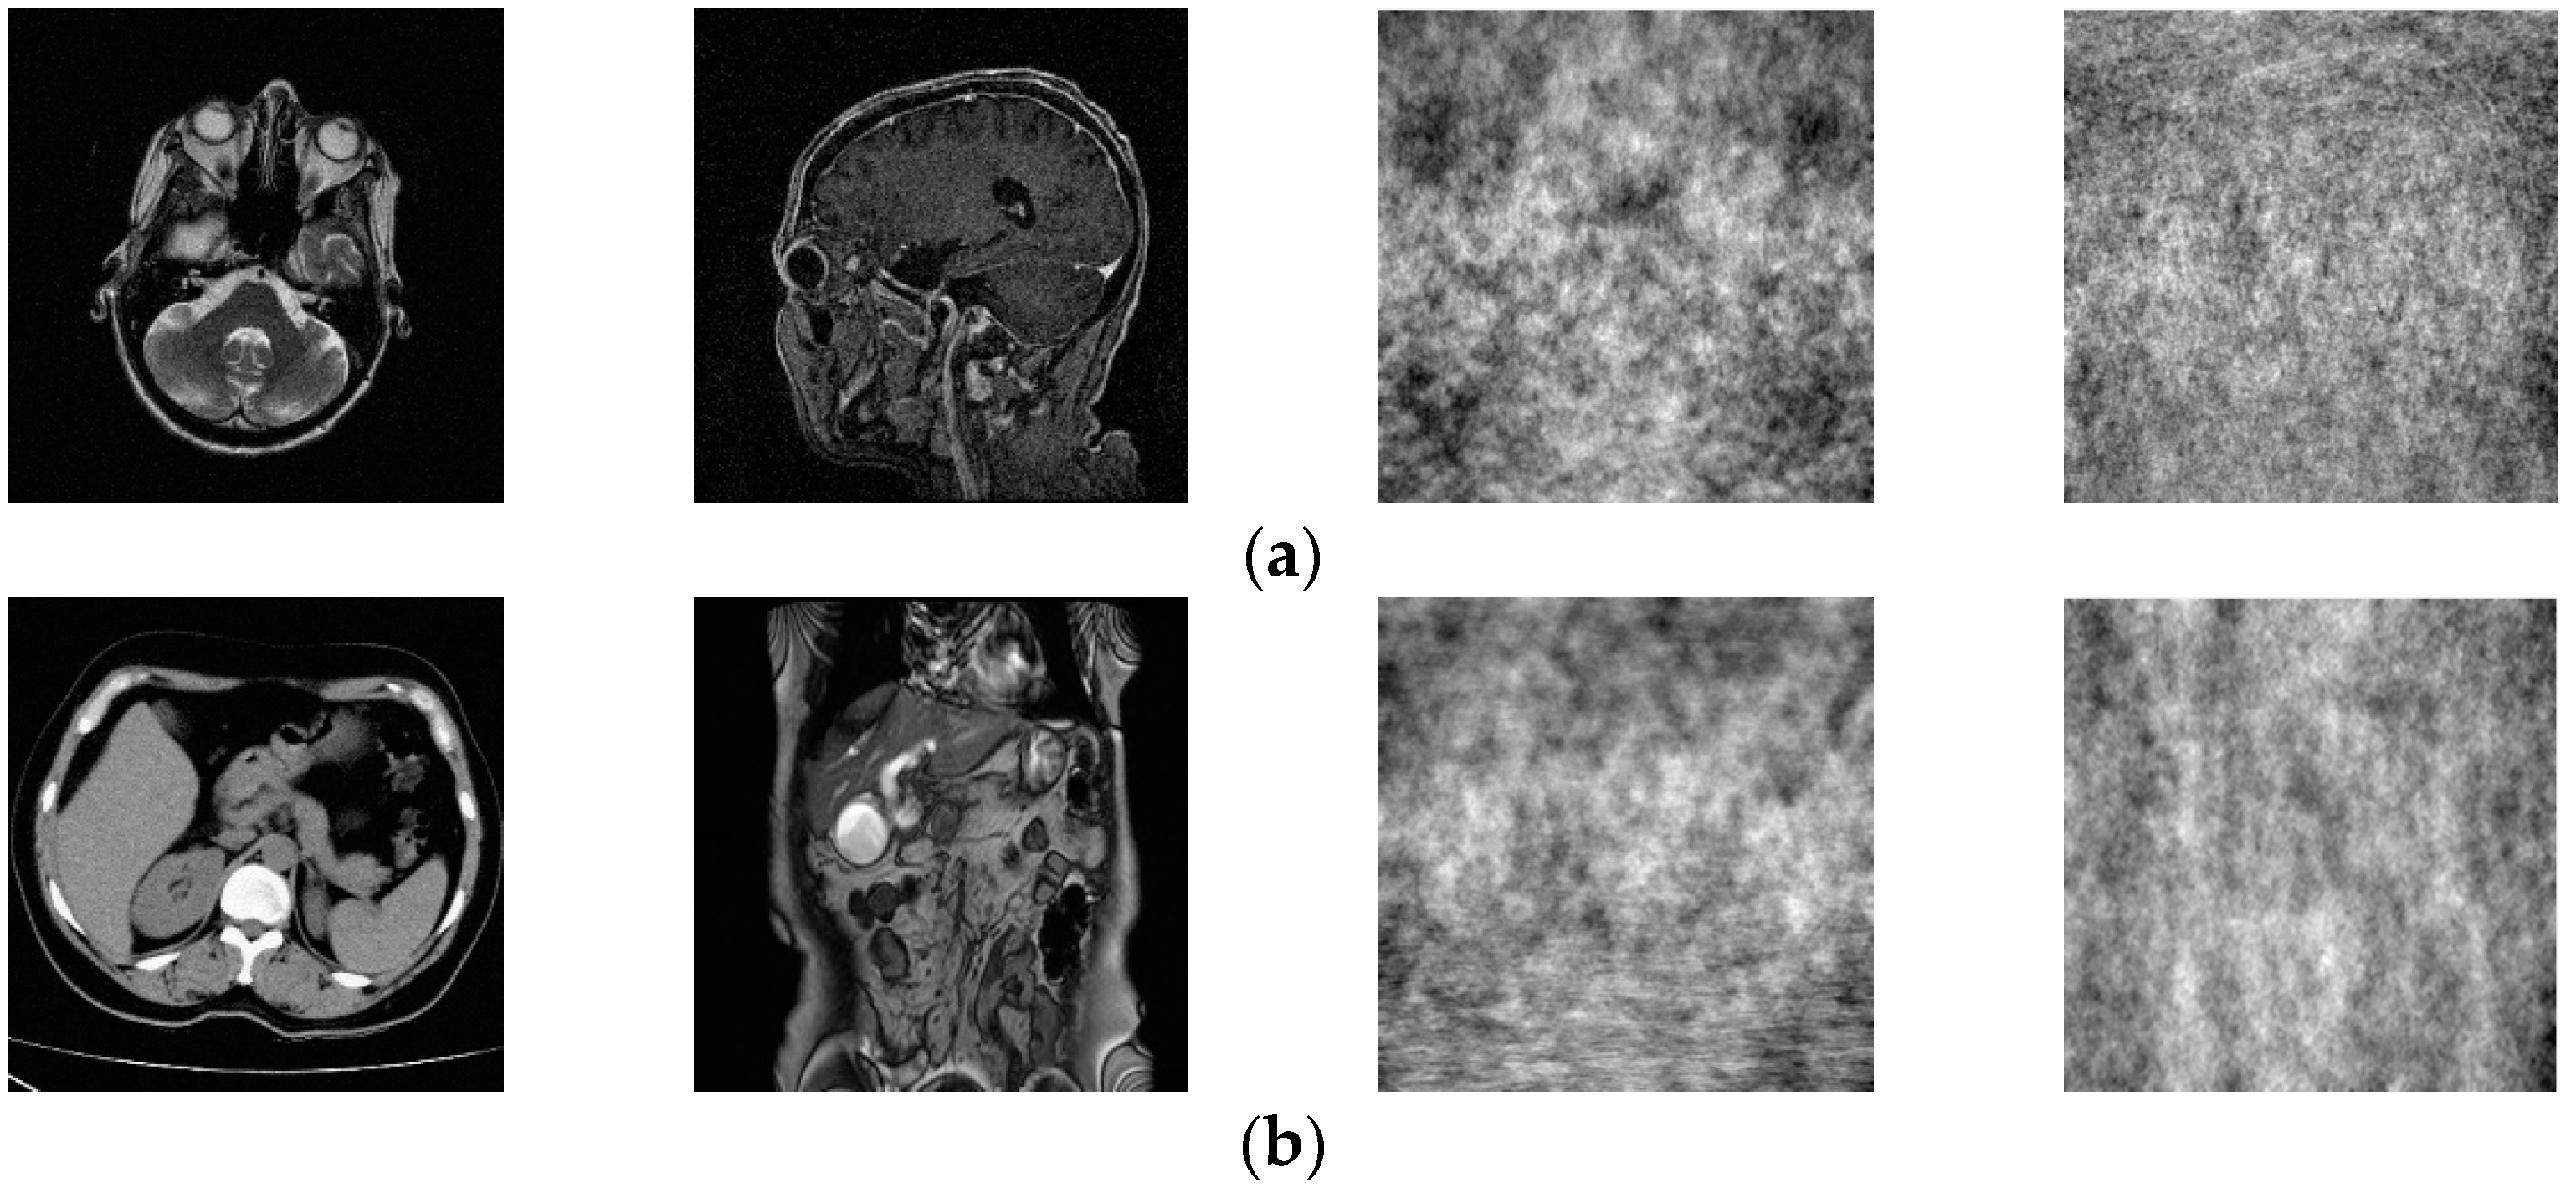

3.2.2. Data Set Creation

The medical image data selected for this paper comes from the Medical Imaging Park and American Research Institute, Inc., which contains tens of thousands of medical images. In this paper, we selected 125 medical images in each of the five major categories of brain, pelvis, bone and muscle, colon, and chest from the website as dataset 1, and encrypted these 125 medical images to obtain 125 encrypted medical images as dataset 2. Some of these 250 images are shown in Figure 5. Data sets 1 and 2 are completely disrupted, respectively, and then divided into three parts in the ratio of 3:1:1: the training set, validation set, and test set. In order to improve the robustness of the network in extracting features, in this paper, the training set and the validation set are enhanced with the data separately, as shown in Table 1. Thus, we obtained 12,850 images as the total dataset for this training. Because the input size of the DarkNet53 convolutional neural network is 2,562,563, all medical images are resized to 2,562,563 here. For the production of dataset labels, this paper first performs DCT on the images of the training and validation sets and then selects the 128-bit feature vectors of the low-frequency part as labels.

Figure 5.

Two original images and corresponding encrypted images for each type of image. Brain image (a); abdominal pelvis image (b); bone muscle image (c); colon image (d); and chest image (e).